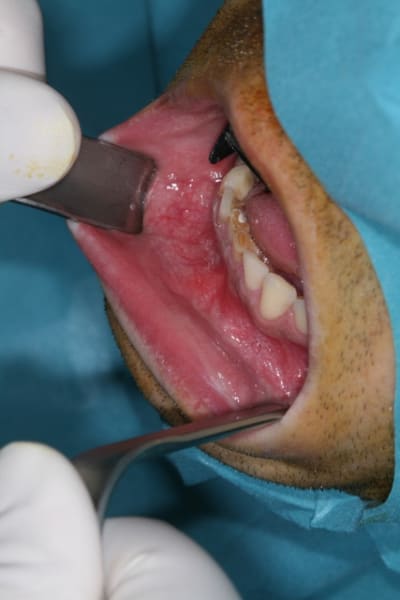

tu avais une épithélialisation dans ta cavité, un liquide une avec couleur et un aspect similaire à un subtile mélange de nutella et de moutarde ? ou un trou vide ?

Non c'était un kyste d'origine dentaire à l'apex de 31 qui est lié à une nécrose après trauma 20 ans plus tot.

La lésion est d'ailleurs en anapath